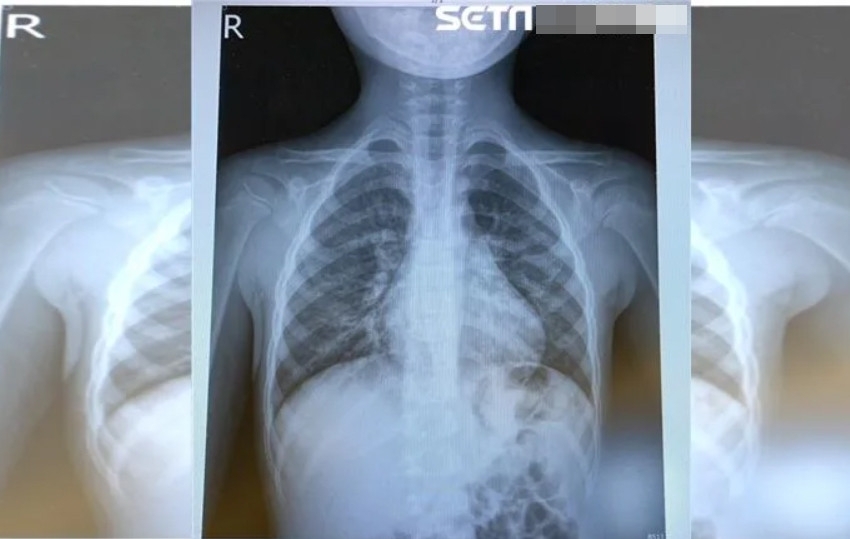

Số người nhiễm virus HMPV ảnh hưởng đến phổi tăng lên trong mùa đông năm nay của Trung Quốc. (Ảnh: BSCC)